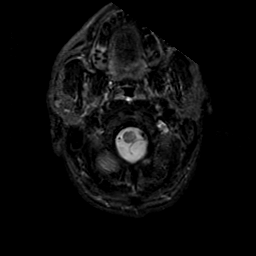

MR Study #23, January 26, 1992 -- Slice #2